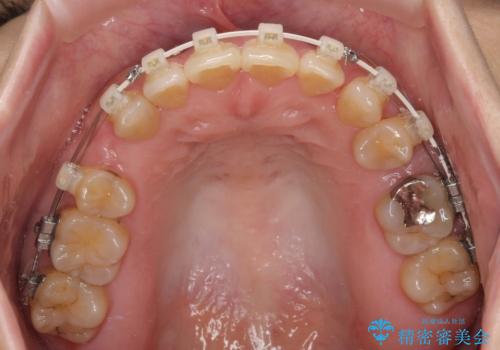

- 矯正装置

- 審美装置

- 前歯のデコボコと口元の突出感を気にして来院された患者様です。

上下前歯がくちばしのように突出していたため、上下左右の第一小臼歯4本を抜歯し、ワイヤー装置にて矯正治療を行うこととしました。

上顎骨に対して下顎骨がやや前方位に位置しているため、歯肉退縮を回避するために下顎前歯をあまり内側に移動させることができない状況でしたが、十分に口元の突出感を改善することができました。